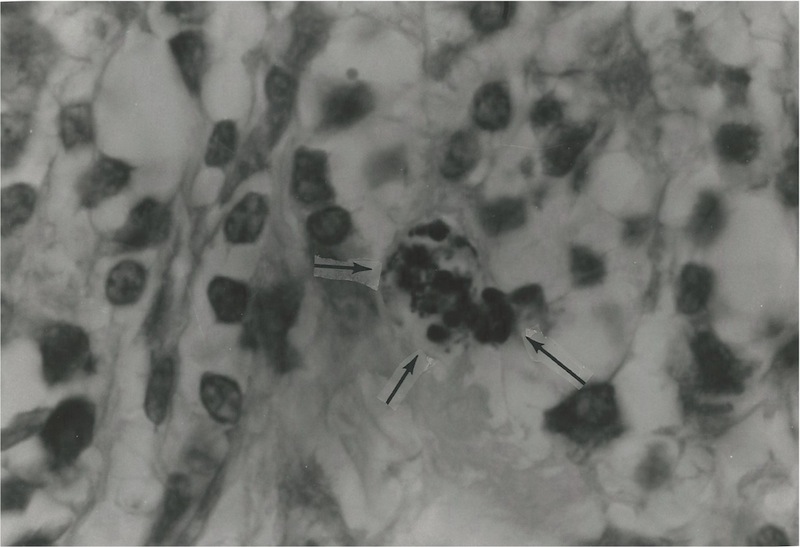

Figure

3. Tissue section of breast cancer showing intracellular variably-sized

coccoid forms and larger globoid forms. Intensified Kinyoun stain. x

1000, in oil